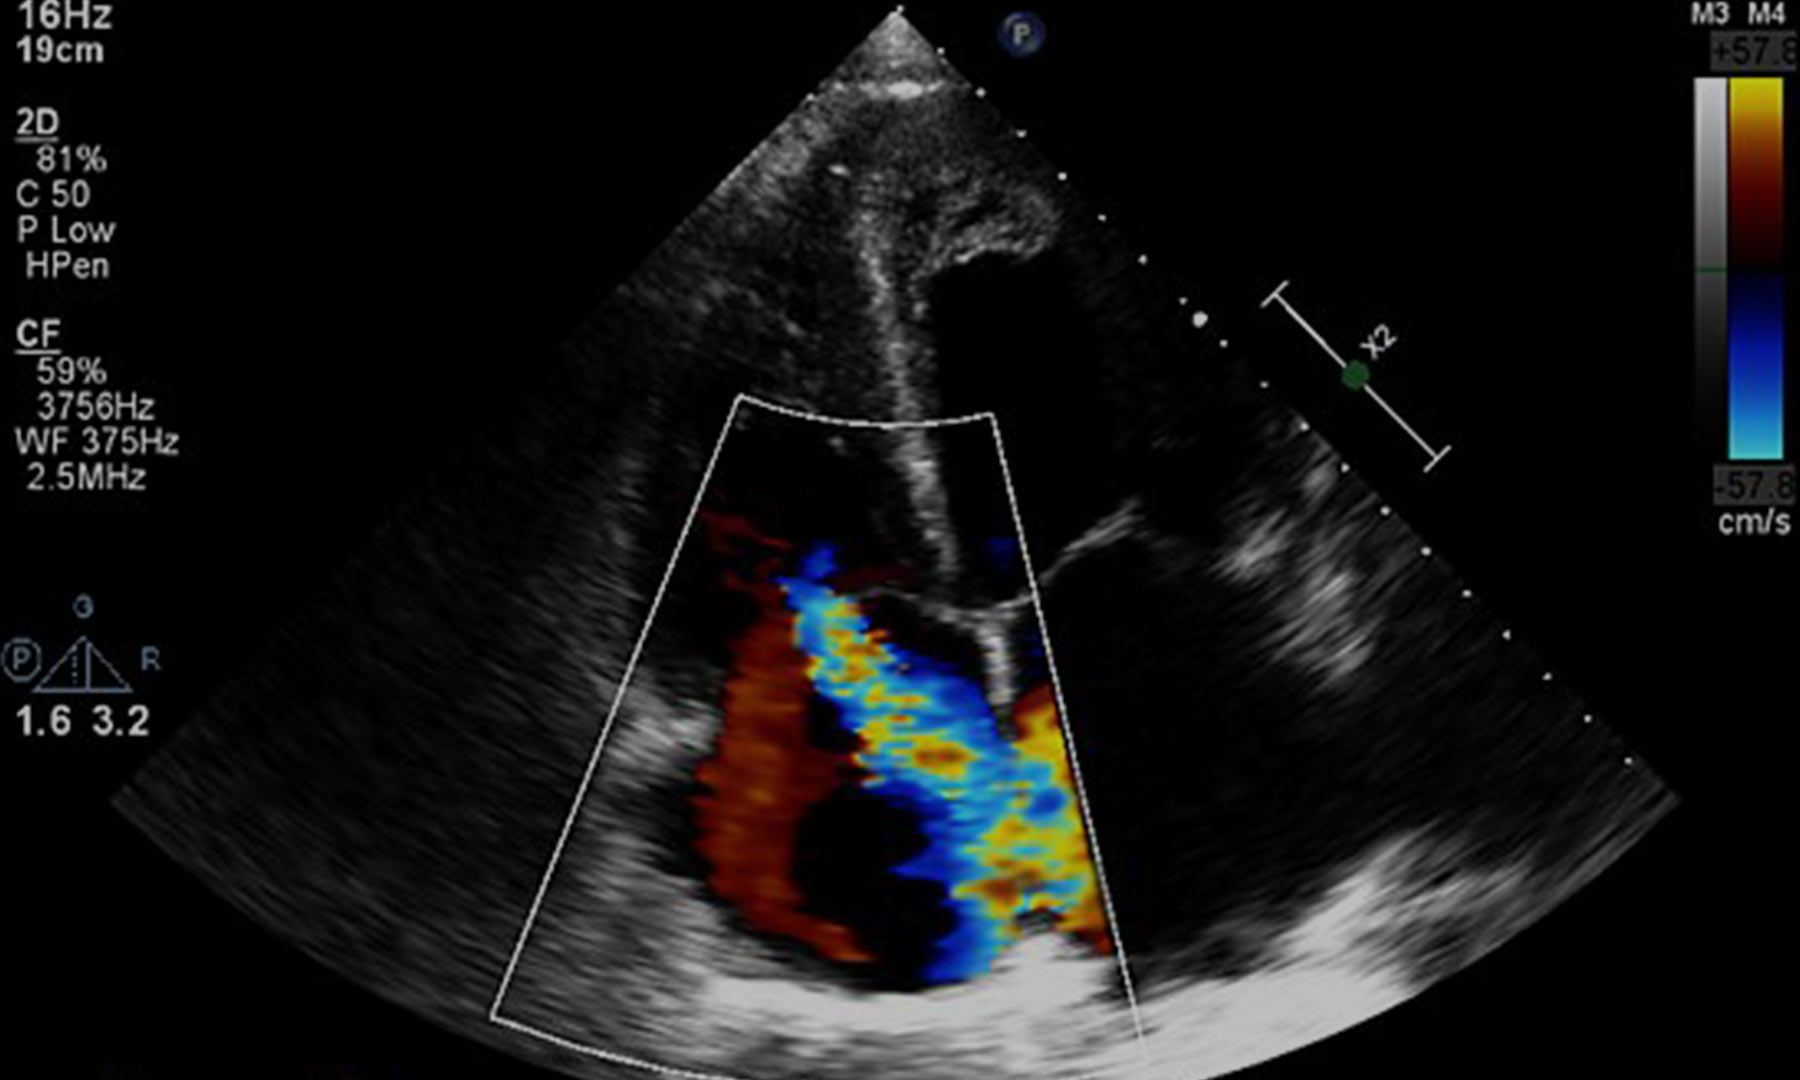

Designed to meet the evolving demands of modern healthcare, the program emphasizes diagnostic imaging, critical thinking, professionalism, and clinical competency across abdominal, obstetrical/gynecological, and related sonographic specialties. Students complete comprehensive didactic coursework, specialty-focused sonography education, and extensive supervised clinical experience to ensure graduates are workforce-ready and prepared for professional credentialing.

Diagnostic medical sonography is a non-invasive imaging profession that uses high-frequency sound waves (ultrasound) to produce dynamic visual images of organs, tissues, and blood flow within the body. Sonographers play a vital role in patient diagnosis, care, and interdisciplinary healthcare collaboration.

- Supervised abdominal, obstetrical/gynecological, and specialty sonographic imaging procedures